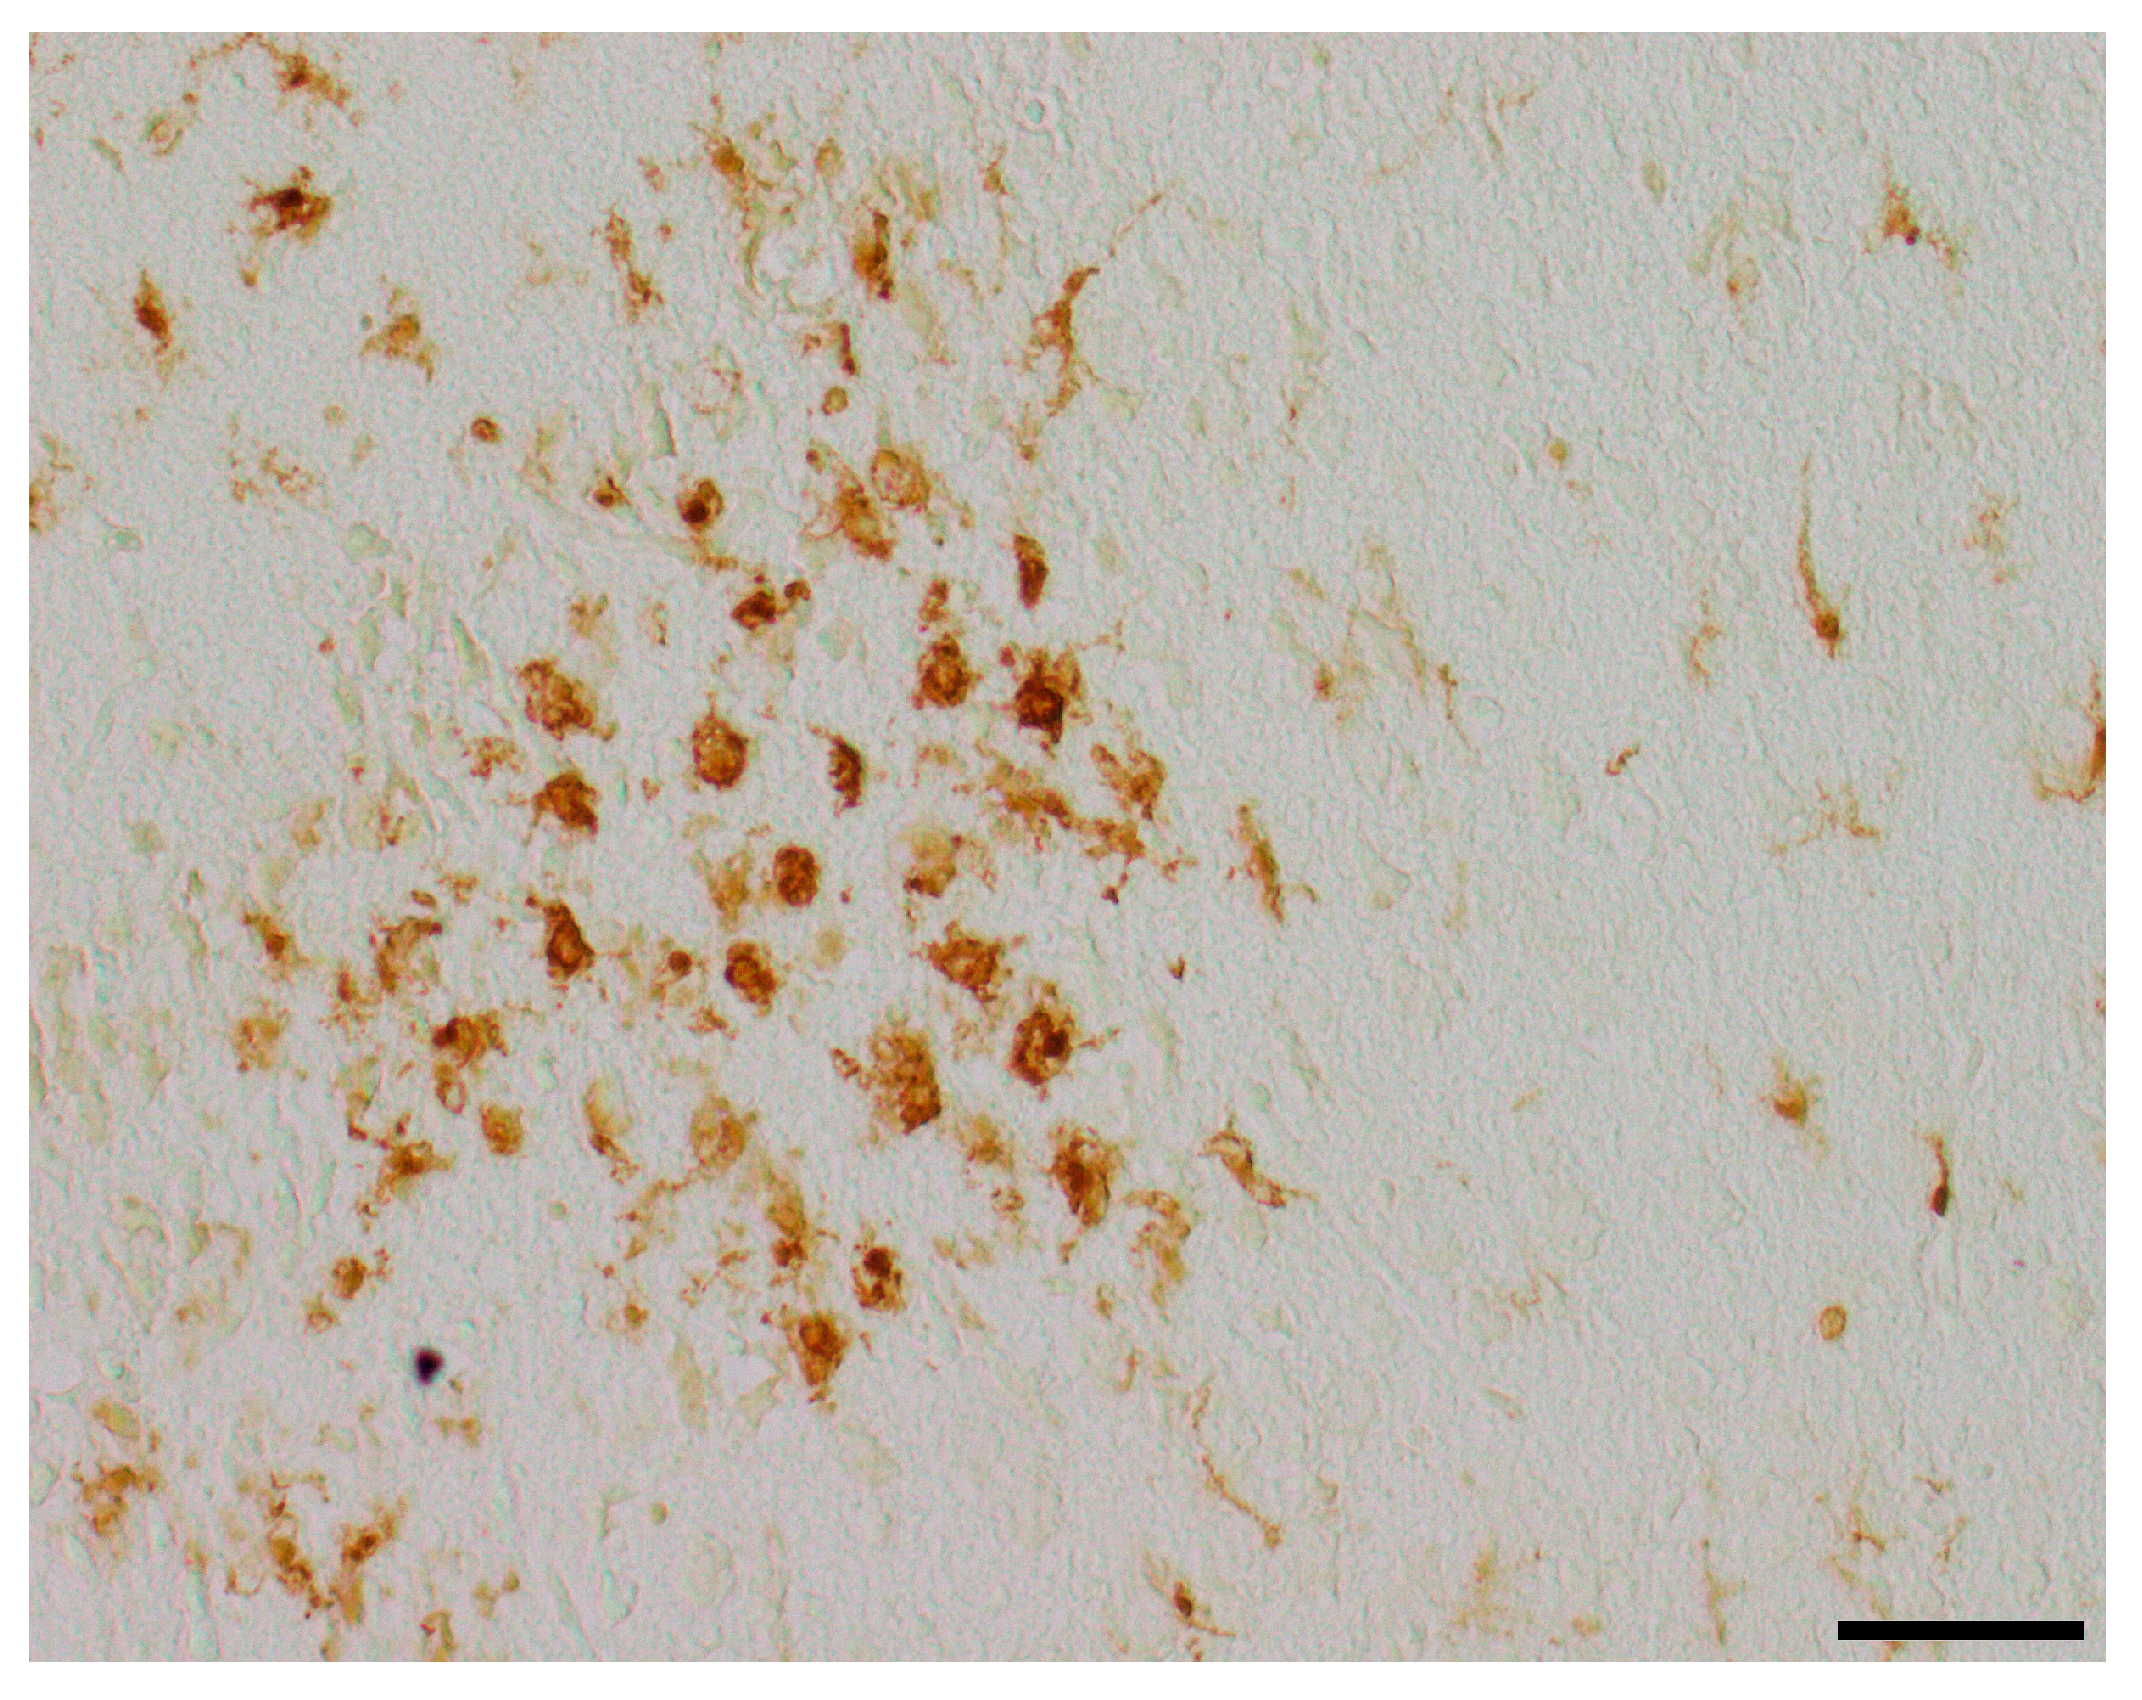

3.4. Microglial Cell Activation

| Section Plane | Hemisphere | Brain Region | Treatment Group | Number of Positive Cells, Median (25th; 75th Percentile) | p-Value |

|---|---|---|---|---|---|

| Occipital | Contralateral | White matter | |||

| Control | 11 (4; 12) | ||||

| Solvent control | 6 (4; 10) | ||||

| DHEA 0.1 µg/g bw | 6 (4; 11) | ||||

| DHEA 1 µg/g bw | 13 (11; 16) | ||||

| DHEA 10 µg/g bw | 10 (6; 14) | ||||

| DHEAS 0.1 µg/g bw | 11 (3; 23) | ||||

| DHEAS 1 µg/g bw | 7 (6; 10) | ||||

| DHEAS 10 µg/g bw | 8 (6; 11) | 0.268 1 | |||

| Ipsilateral | White matter | ||||

| Control | 125 (12; 181) | ||||

| Solvent control | 16 (4; 162) | ||||

| DHEA 0.1 µg/g bw | 19 (11; 111) | ||||

| DHEA 1 µg/g bw | 182 (10; 282) | ||||

| DHEA 10 µg/g bw | 27 (10; 141) | ||||

| DHEAS 0.1 µg/g bw | 121 (7; 248) | ||||

| DHEAS 1 µg/g bw | 25 (9; 228) | ||||

| DHEAS 10 µg/g bw | 83 (17; 230) | 0.836 1 | |||